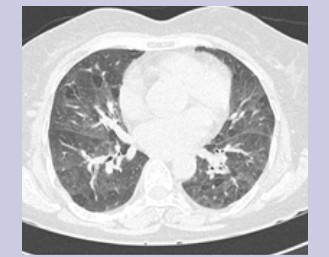

Physical exam was benign. Complete blood count and immunological panel were within normal limits. Spirometry, lung volumes and diffusion capacity were within normal limits. Chest x-ray (Figure 1) showed faint reticular opacities prominent in the mid to lower lobes. Computed Tomography (Figure 2) of the chest showed a diffuse mosaic attenuation pattern. There were multiple pulmonary nodules noted in the right middle lobe. There was no lymphadenopathy. Transthoracic echocardiogram showed impaired left ventricular relaxation with normal LV ejection fraction. Bronchoscopy and transbronchial biopsies of the right upper, middle and lower lobes were performed. Histopathology (Figure 3, Figure 4) revealed mild, nonspecific chronic inflammation. Acid-fast bacilli and fungal stains were negative. There was no evidence of malignancy. Given the persistent symptoms and abnormal CT findings, wedge biopsy of the right upper, middle and lower lobes was performed. Wedge resections showed alveolated lung with expansion of peribronchiolar interstitium by black dust-laden macrophages and dust macules. There were areas of peribronchiolar fibrosis with birefringent silicate and silica material within the interstitium and macrophages. Based on her history of exposure to stone grinding, charcoal and wood burning stoves along with the histopathologic findings consistent with mixed dust pneumoconiosis, she was diagnosed with "Hut Lung” or Domestically Acquired Particulate Lung Disease.

Figure 2: CT Thorax showing diffuse mosaic attenuation bilaterally.